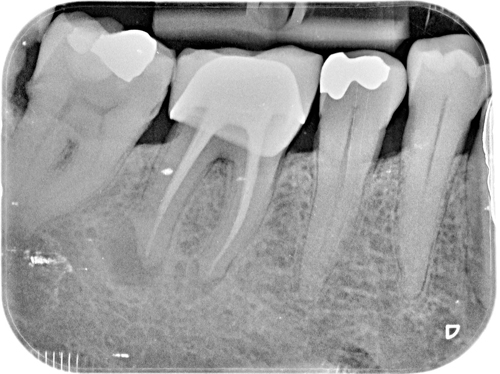

Nuestro paciente Eduardo Vicente Pedrós ha tenido en varias ocasiones infecciones en dientes que estaban desvitalizado. Él nos explica perfectamente en el vídeo que la cirugía periapical (o apicectomía) es un tratamiento que permite salvar la mayoría de los dientes afectados de esta patología.

Es una intervención técnicamente exigente, que requiere formación e instrumentos especializados (microscopio, endoscopio, etc.), pero que correctamente realizada no causa molestias prácticamente y tiene unos resultados exitosos en más del 90% de los casos.

Los implantes son una buena herramienta, pero sin duda lo mejor son los propios dientes naturales. Con la cirugía periapical nuestros pacientes tienen la oportunidad de conservar sus propios dientes afectados de infección en el hueso periapical.